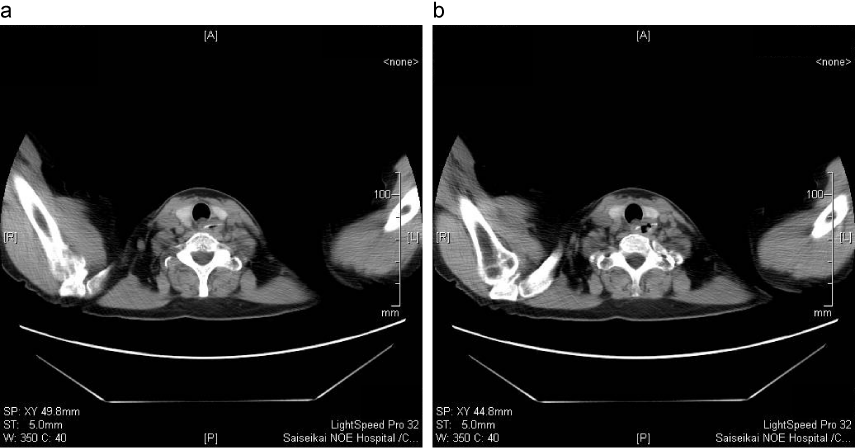

小腸異物(義歯)例

a:経過観察(2日目):異物は肛門側へ進んでいることが示唆される。

b:経過観察(3日目):同上

c:経過観察(4日目):同上 この後、便中に異物(義歯)の排出を確認した。

出典